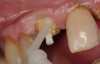

A Class IN maxillary bicuspid was previously restored with a fiber post and an all-porcelain crown (Figure 1). The forces of the oral environment resulted in fracture of the fiber post and crown failure. The remaining fiber post in the root was removed, and anti-rotational areas were prepared for a cast post (Figure 2). A gold cast post was constructed at a dental laboratory, using an indirect technique (Figure 3). A porcelain-fused-to-metal (PFM) crown was constructed with a bevel finish to provide a ferrule and reduce forces on the post (Figure 4 and Figure 5).

Figure 5  The final crown.

Figure 5